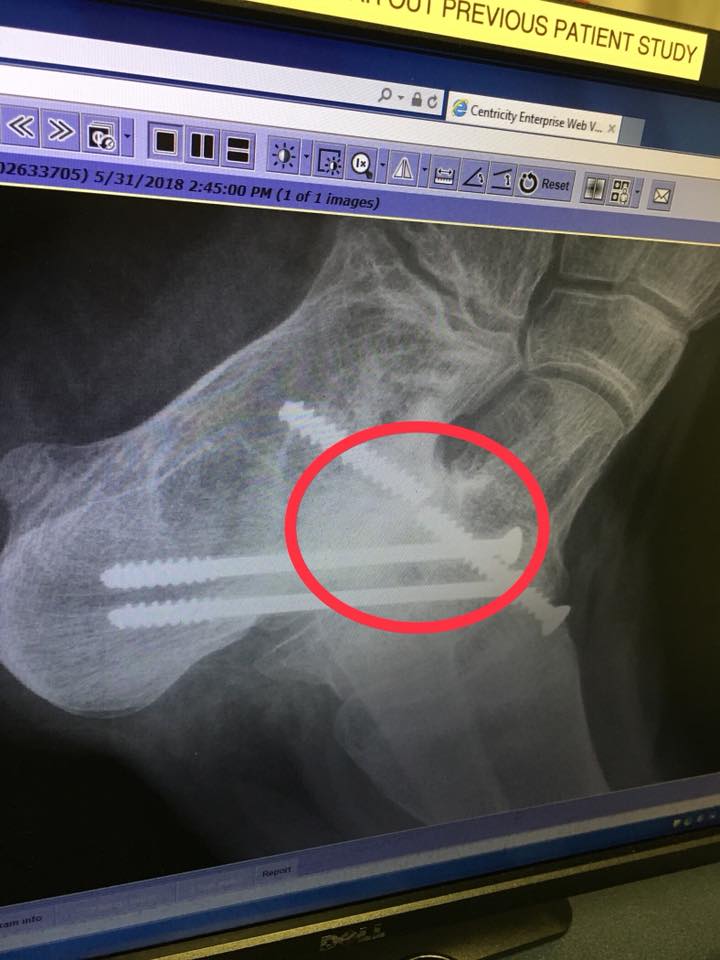

So here is what is happening:� the cadaver bone in his left foot is

completely gone and the open space must have created such a torque in his step

that it snapped one of the 3 screws in that foot right in half. �Yes, he is stronger than titanium.�

So, the surgeon is going to try and remove the broken screw, but he may have to leave the back half in, if the bone around it is too brittle.� In addition, the right foot�s cadaver bone is hanging on by one corner and is very lacey. The doctor is going to replace both of the cadaver bones with bone harvested from the crest of his own hipbone.�

| Broken titanium screw |